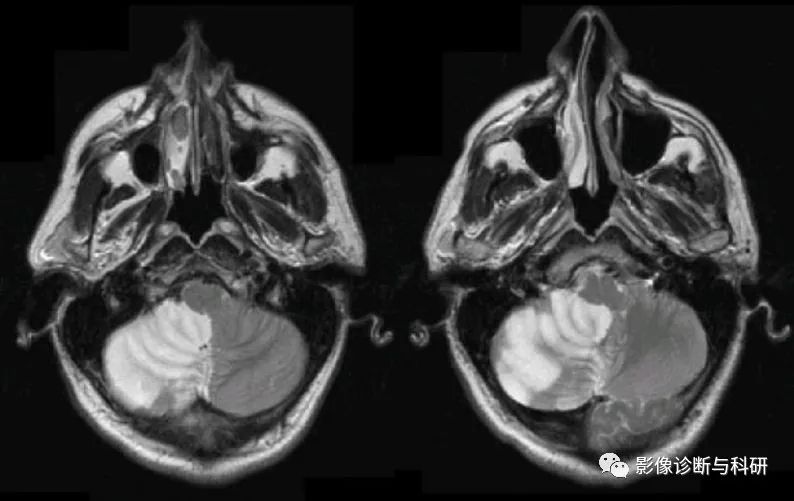

弥散加权图像显示右侧脑桥下外侧、脑桥臂和小脑上有高信号病变(a)。MRA( b),(c)显示右小脑前下动脉(AICA)未见显影